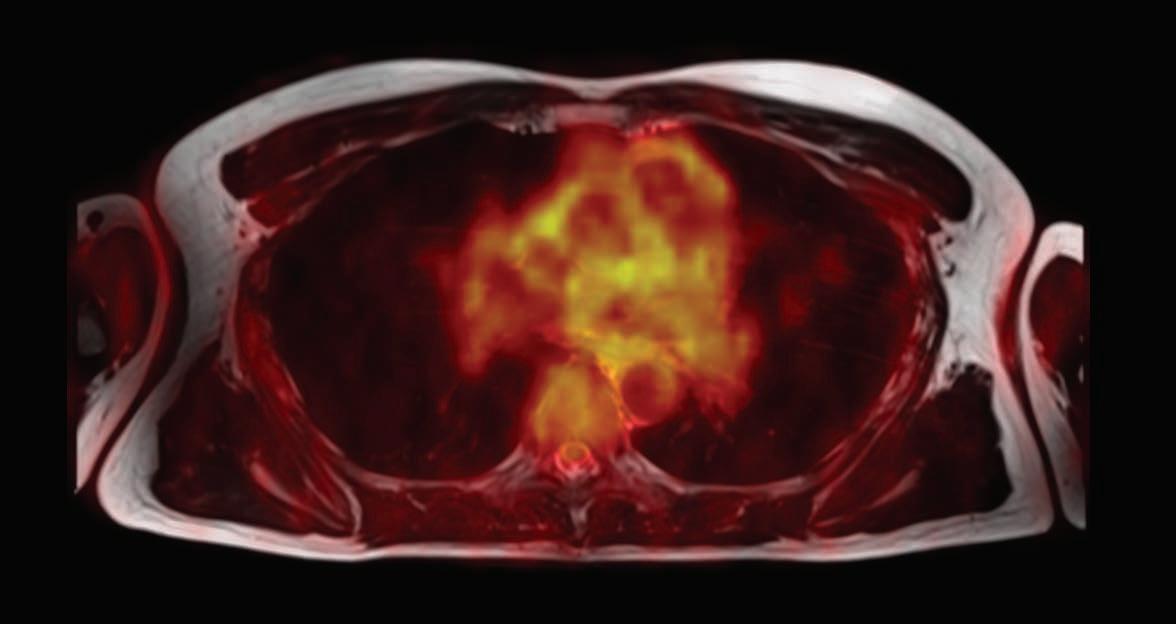

Comparison of Neural Pathways for Deep Brain Stimulation in Human and Nonhuman Primate Brains Magnetic Resonance Imaging (MRI) diffusion tractography (imaging) illustrates the impact of deep brain stimulation in different neural circuits as treatment for neuropsychiatric conditions, including depression (shown in red), obsessive-compulsive disorder (OCD, shown in yellow), and Parkinson’s disease (PD, shown in green and blue).